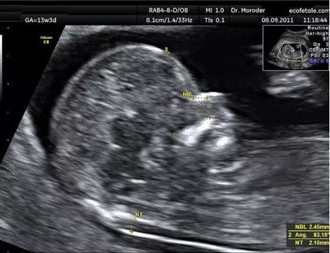

检查时间:1次,11~13周,建议做,最好预约在12周第1~6天。

“NT”是”颈项透明层”的英文简写,这个透明层,是10~13周胎宝宝流动在颈项后面的一层半透明蛋白膜,可以用B超来成像,所以我们通常说B超NT。

正常胎儿的NT厚度应该在3.0mm以内。超过这个正常值,NT越厚,唐氏儿等风险就越大。

上图左上角的GA-13w3d,表示检查时间是孕13周第3天。

图片下方标记为NT的两个+之间的区域,就是“颈项透明层”,这个厚度就是NT值。